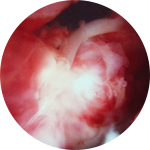

The iliopsoas tendon is one of the main flexors of the hip. Irritation of this tendon, called Iliopsoas tendonitis, can be a common source of hip or groin pain caused from an injury, overuse, or irritation from a total hip replacement. Synovitis is an irritation or inflammation of the lining inside the hip joint, commonly seen with other problems inside the joint. Synovitis is treated with debridement using specialized shavers.

Synovitis is an irritation or inflammation of the lining inside the hip joint, commonly seen with other problems inside the joint. Synovitis is treated with debridement using specialized shavers. Hip arthroscopy can trim out the unstable cartilage, or in some cases perform a microfracture of the bone to stimulate the growth of new cartilage.